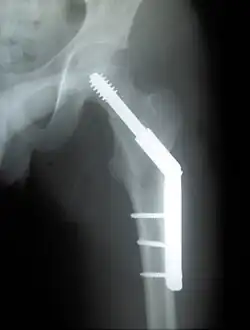

Pertrochantere fractuur

De kans dat een pertrochantere fractuur goed geneest, is groot. Behandeling vindt meestal plaats met een dynamische heupschroef: een lange schroef gaat dwars door de fractuur de heupkop in, en wordt op zijn plaats gehouden met een plaatje dat langs het bot van het dijbeen zit geschroefd met enkele schroeven. Meestal is deze botbreuk binnen de 3 tot 6 maanden genezen. Het is, zeker bij ouderen, niet gebruikelijk de dynamische heupschroef weer te verwijderen; de risico’s van een tweede operatie en eventueel van een nieuwe fractuur zijn groter dan de kans op klachten. Wanneer er sprake is van osteoporose kan de kans op een nieuwe fractuur kleiner gemaakt worden door de osteoporose te behandelen. Bij jonge mensen wordt soms wel overwogen de plaat en de schroeven te verwijderen; bij hen kan het materiaal de spanning op het bot vergroten, waardoor de kans op een nieuwe botbreuk bij een ongeluk juist groter wordt.